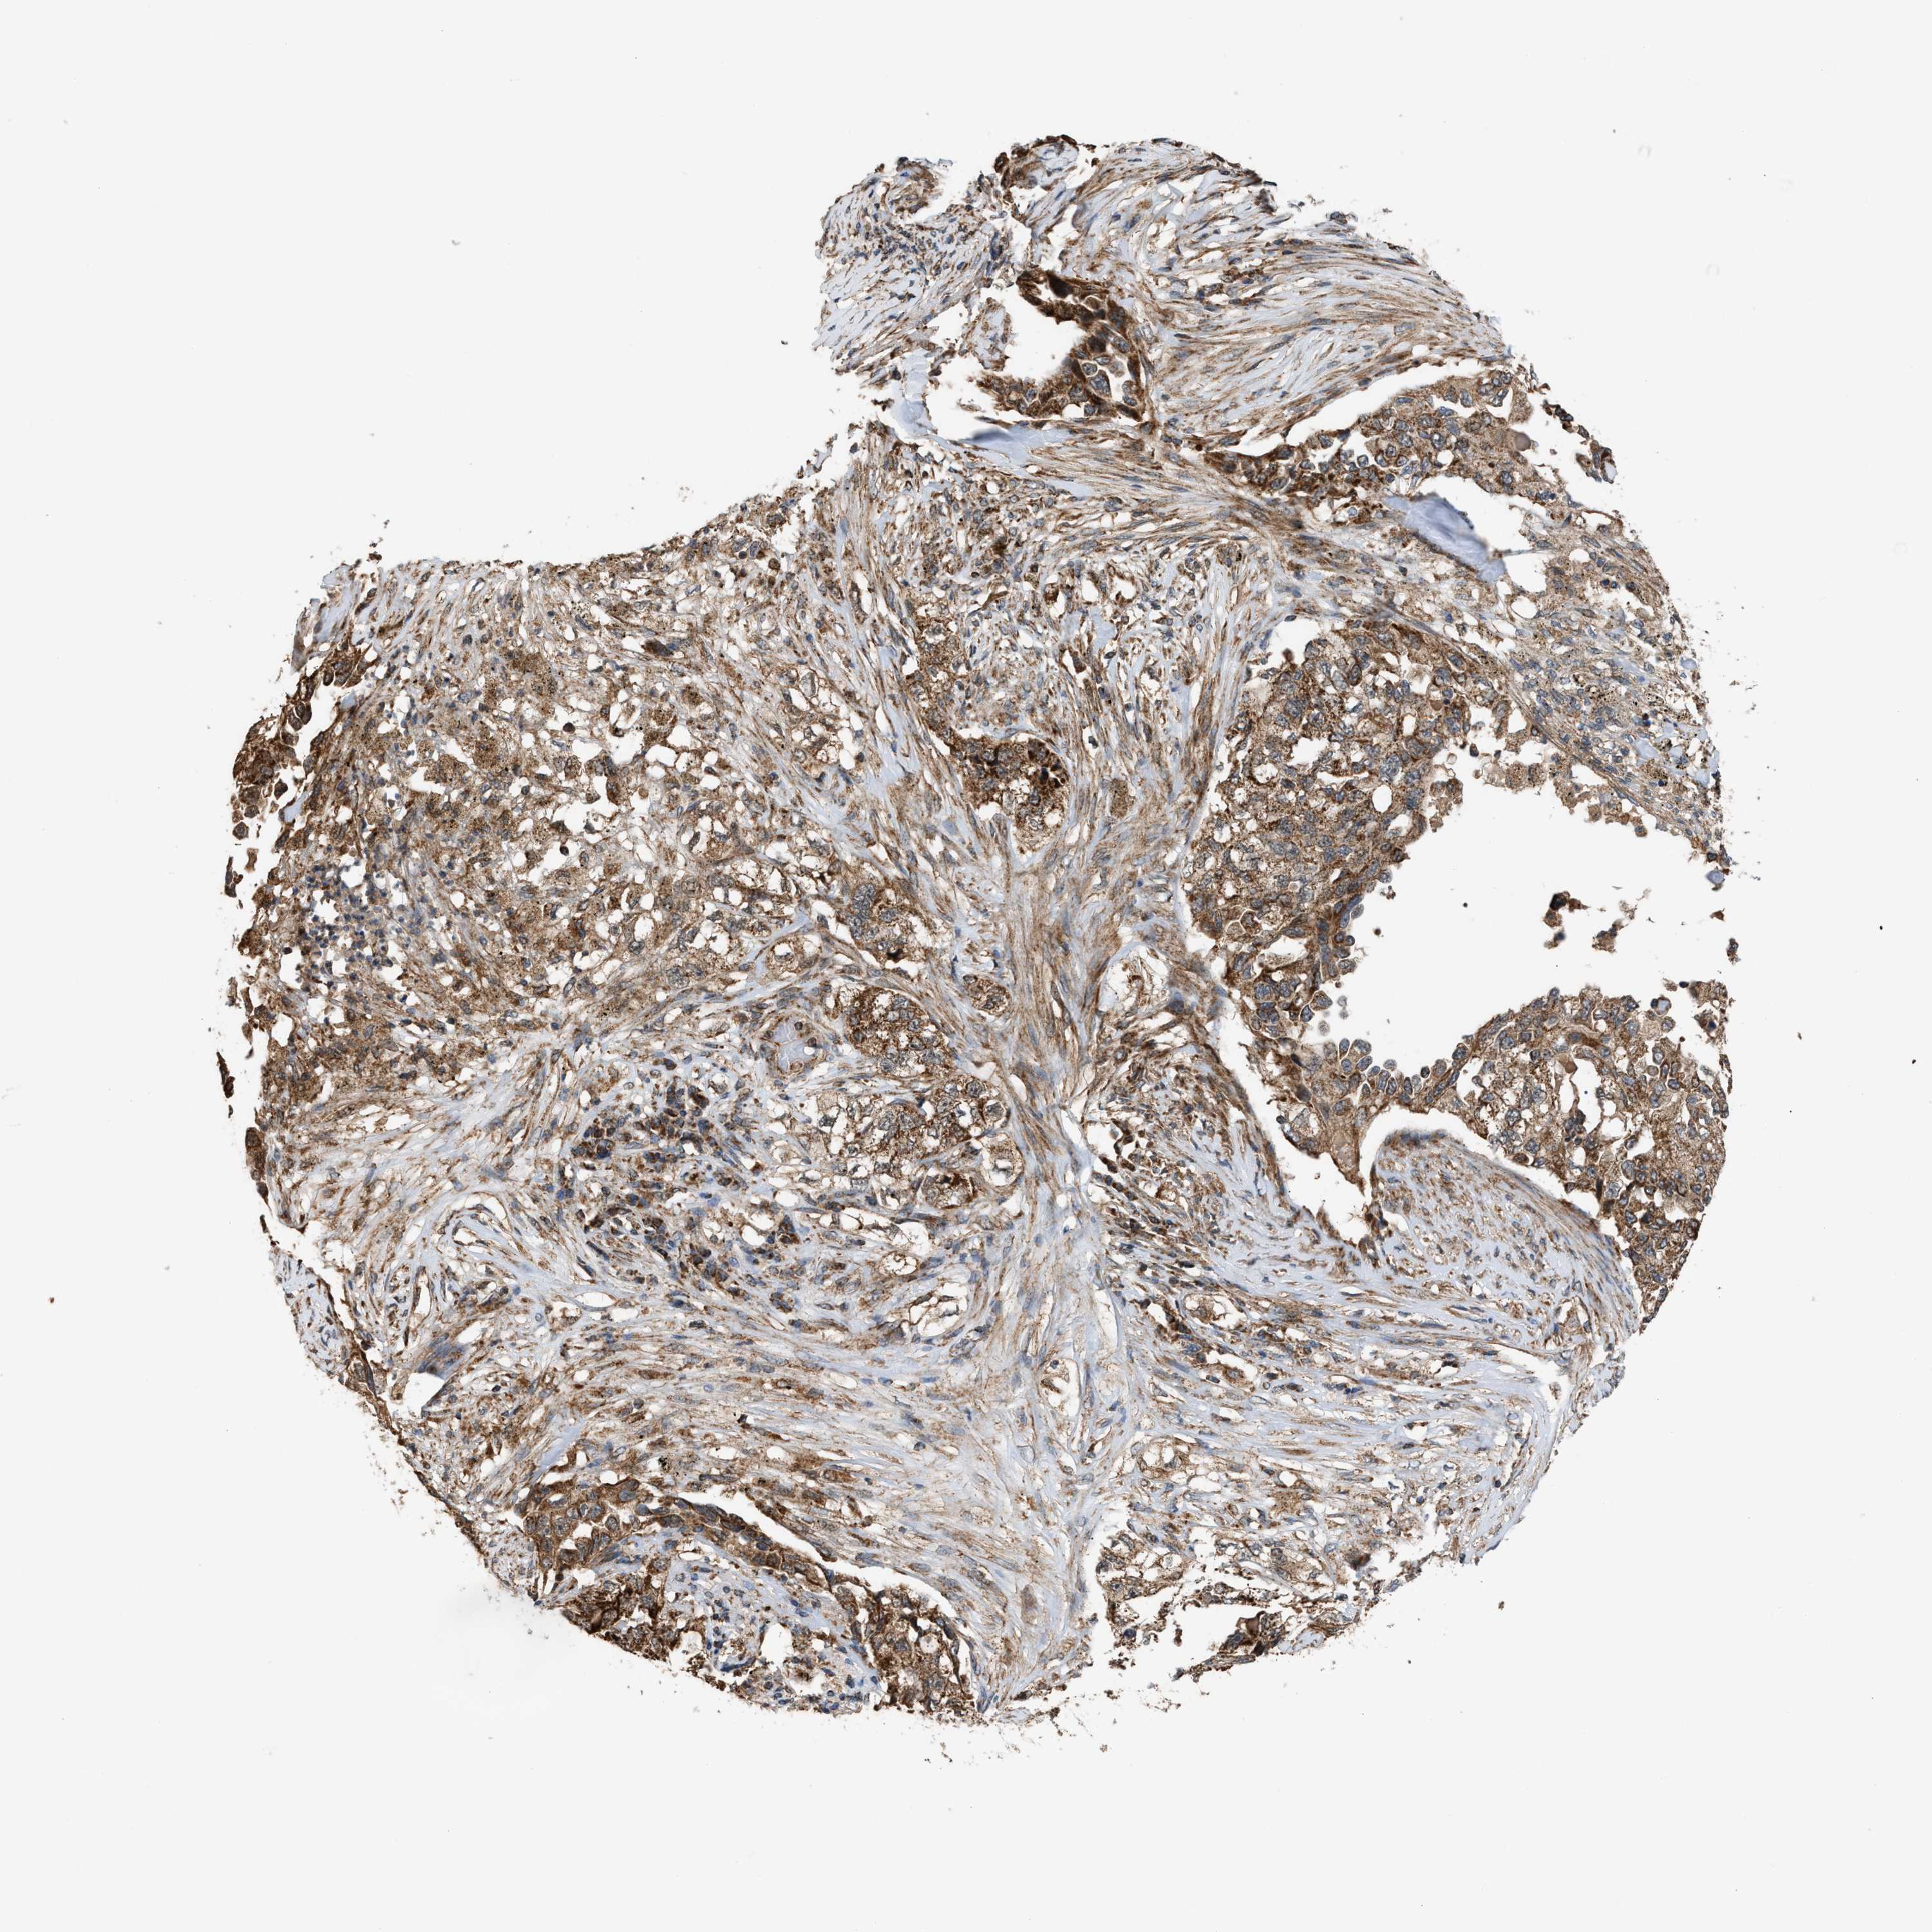

CANCER LUNG CANCER Show tissue menu

LUAD TCGA LUAD VALIDATION LUSC TCGA LUSC VALIDATION PROTEIN LUAD CPTAC PROTEIN LUSC CPTAC PROTEIN EXPRESSION